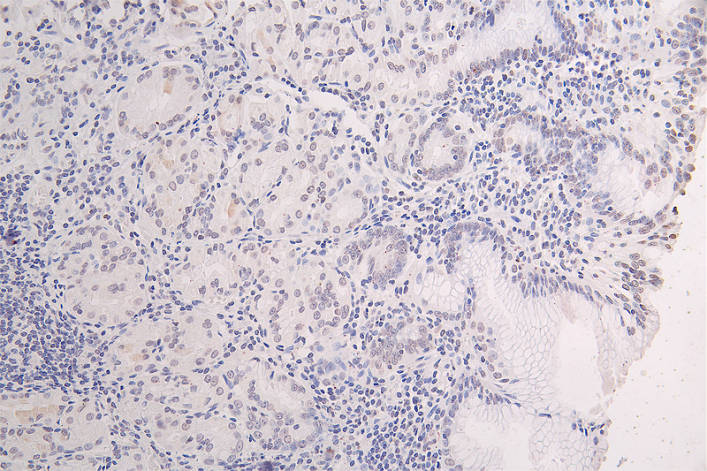

IHC image of CSB-RA051594A0HU diluted at 1:50 and staining in paraffin-embedded human brain tissue performed on a Leica BondTM system. After dewaxing and hydration, antigen retrieval was mediated by high pressure in a citrate buffer (pH 6.0). Section was blocked with 10% normal goat serum 30min at RT. Then primary antibody (1% BSA) was incubated at 4°C overnight. The primary is detected by a Goat anti-rabbit polymer IgG labeled by HRP and visualized using 0.10% DAB.